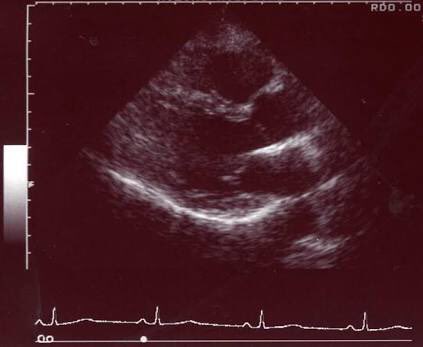

母体の胎児の神秘 音波の秘密(エコー波とオファー波)

超音波から読み解く

妊婦さんの、お腹を診るのはエコー波なのですが